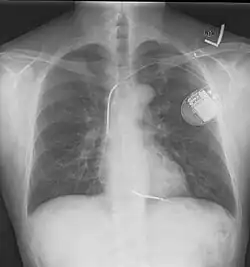

Placa de tórax tomada después de colocar un desfibrilador automático implantable; muestra el generador del aparato en el tórax superior izquierdo y la derivación (electrodo) del aparato en la cavidad del ventrículo derecho. Nótese ambos resortes radiopacos a lo largo de la derivación del aparato. -